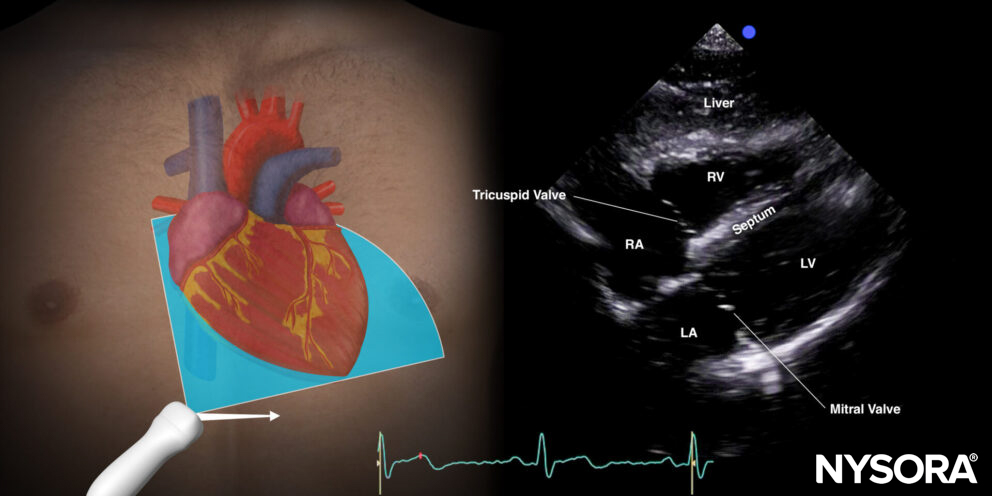

For venous catheter position evaluation, the subcostal 4-chamber view needs to be assessed.

Subcostal 4-chamber view.

9 mL of a saline with 1 mL air mixture (‘shaken’/’agitated’ ) is injected rapidly through the distal port of the central venous line while visualizing the right atrium in the subcostal 4-chamber view.

- Immediate air bubbles: If a transient opacification in the right atrium appears immediately (<2s) following the injection of the mixture, the catheter is in the right position in a large central vein.

- Delayed air bubbles: If the opacification is delayed and appears slower (>2s), the catheter is probably placed at an atypical position in the internal jugular, subclavian, or brachiocephalic vein.

- Absent air bubbles: If the opacification does not appear at all, the catheter is probably malpositioned and may be placed in an artery or extravascular.